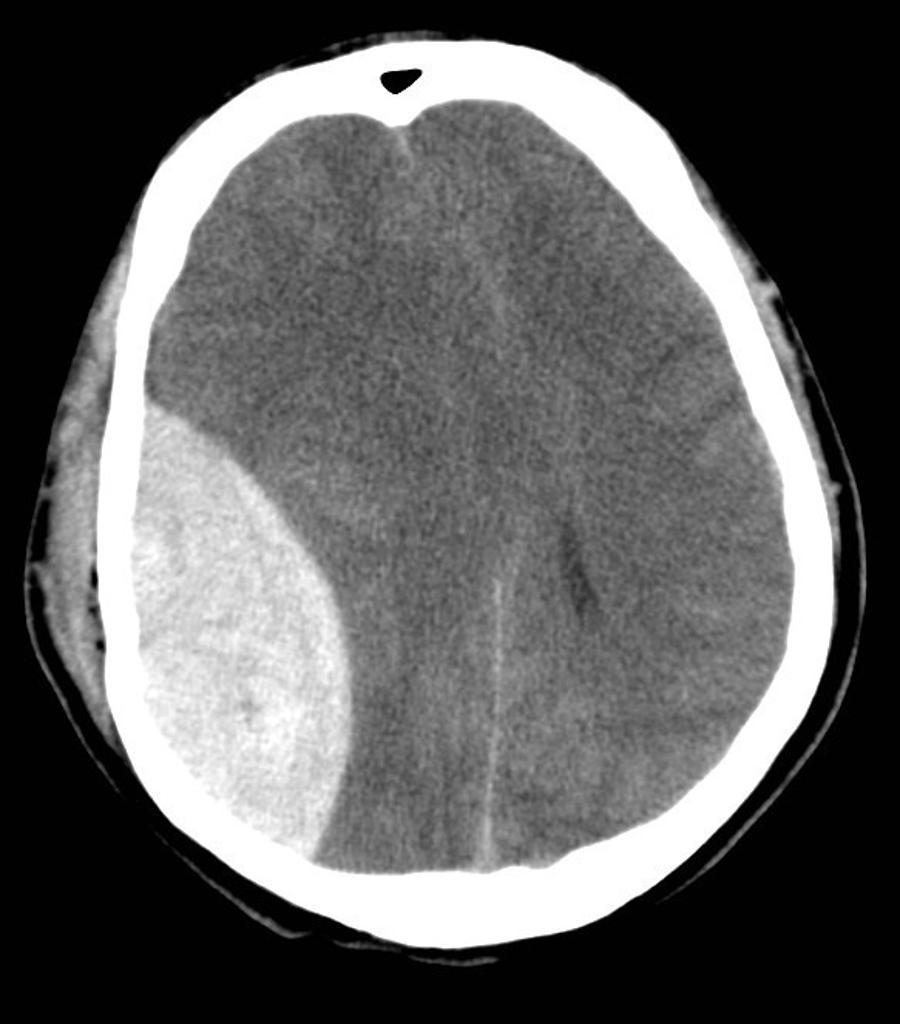

Epidural hematoma

• Hemorrhage between inner surface of skull and outer surface of dura

• Most often from torn middle meningeal artery

• Usually associated with history of head trauma and frequently associated with skull fracture

• Mostly in younger patients (dura less adherant to bone)

• Biconvex in shape (lentiform)

• Limited by sutures, but not by venous sinuses (however in children, up to 11% cross suturelines)

• Exceptions:

• Fracture crosses suture

• Suture diastasis

• Vertex EDH

• Usually unilateral

• >95% supratentorial

• Parietotemporal > Frontal = parietooccipital

• <5% posterior fossa

• Hyperdense, hetrogeneous

• Well-demarcated

• Secondary features of mass effect may be present depending on size (subfalcine herniation, uncal herniation, midline shift)